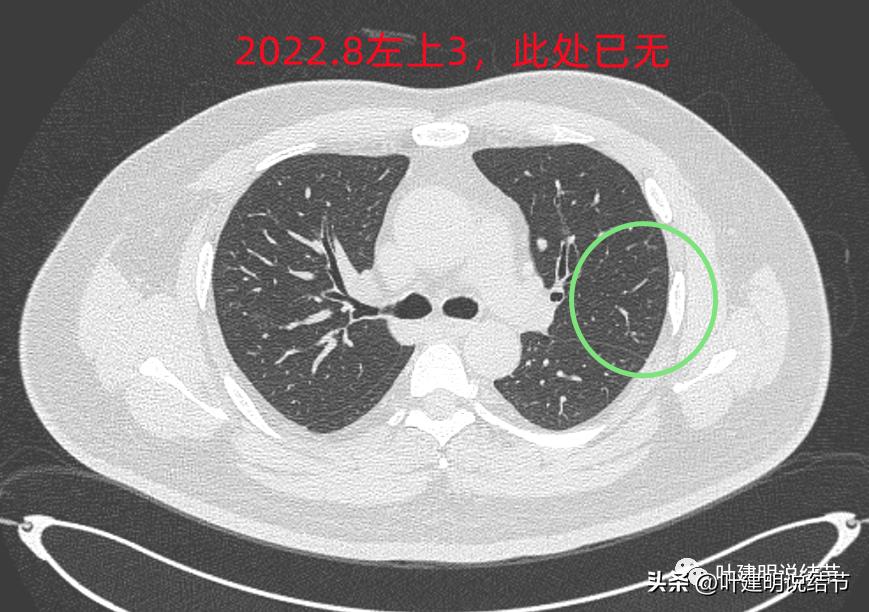

后续再看2022年8月的CT图像,有点惊掉下巴的感觉:

左上叶的病灶1、2、3都没有了!!!完全没有了!那当然说明是炎症性的,居然全部吸收了!

但左上病灶4仍在,形态也没有明显变化,无好转,也无明显进展。这是肿瘤性质的吗?虽然存在2年多了,但因为它的兄弟们都不见了,让我对它认定的肿瘤范畴也产生了怀疑,也许是纤维增生而已呢!